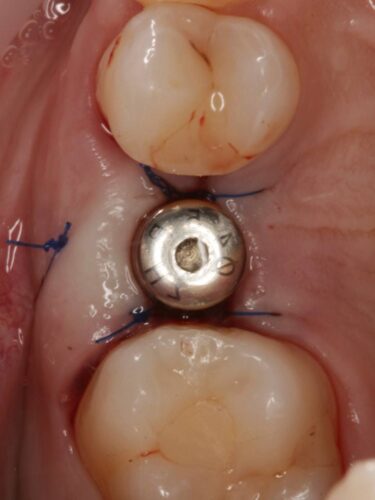

Установка импланта, подшит трансплантат с бугра( для увеличения объема мягких тканей), установлен формирователь десны